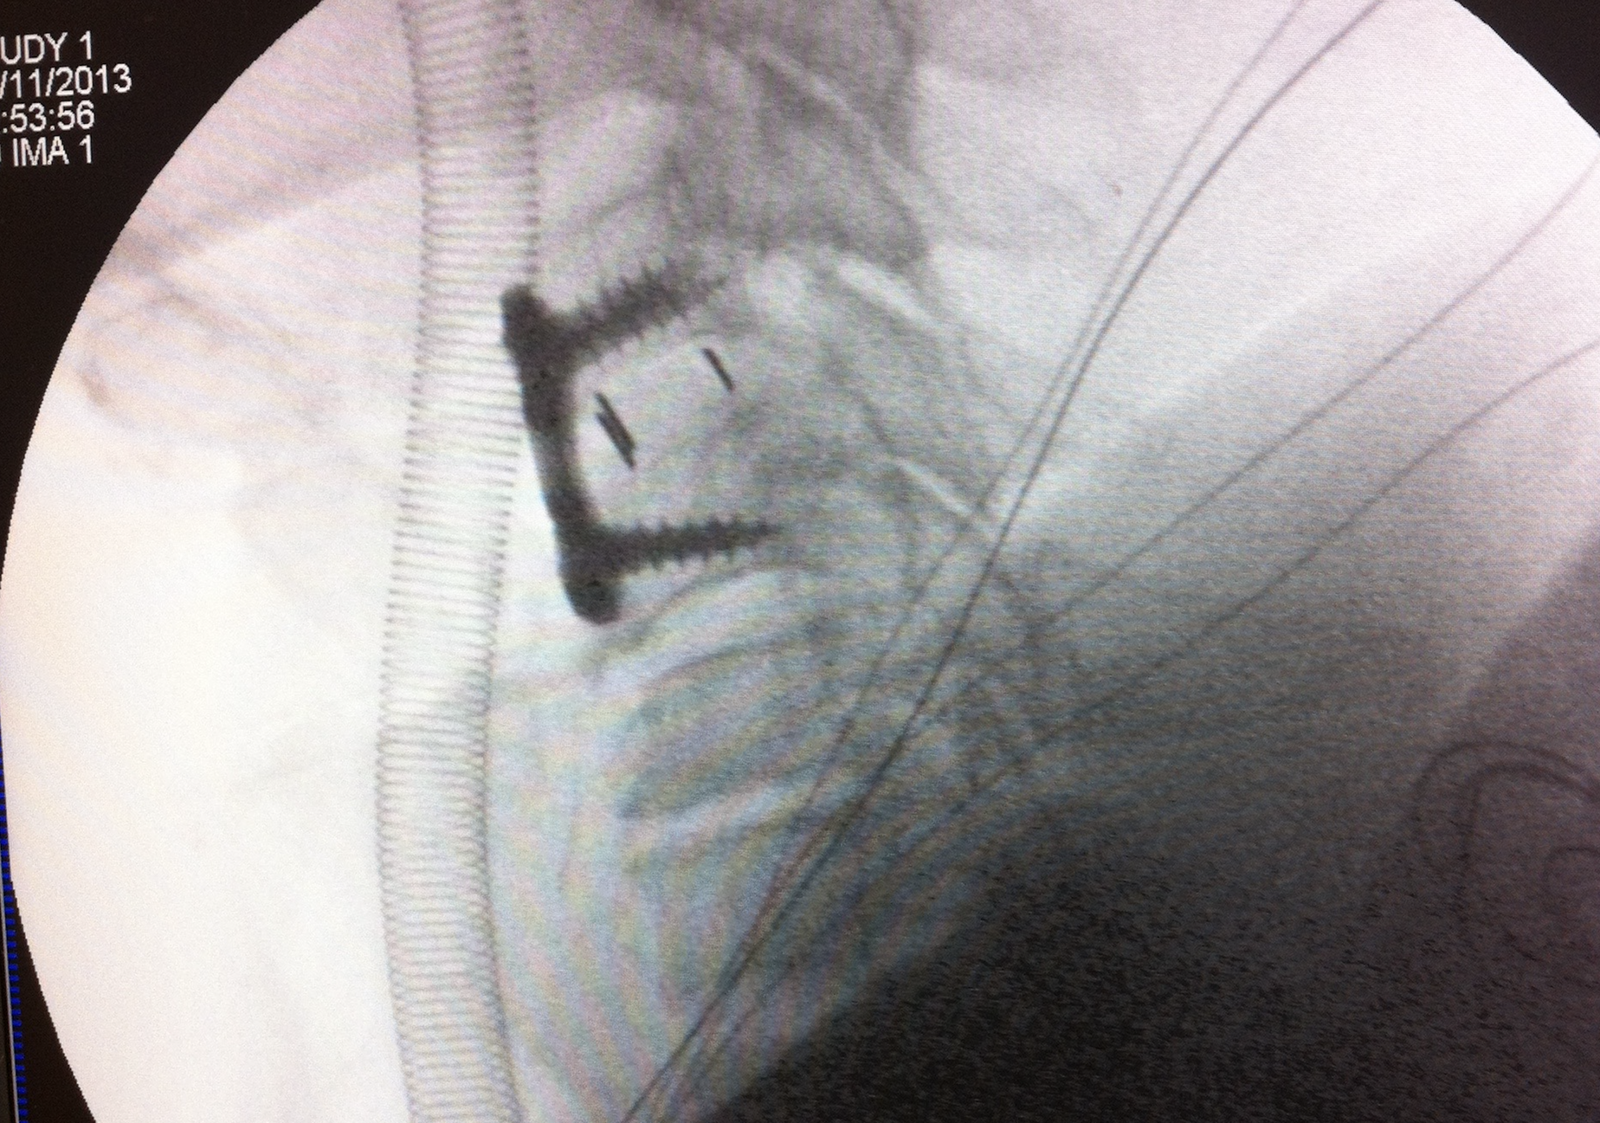

– Durante la intervención, las radiografías intraoperatorias confirmaron la correcta alineación de los cuerpos vertebrales tras la reducción de la luxación.

– Observamos el resultado quirúrgico, incluyendo la cistectomía cervical y artrodesis cervical vía anterior con la colocación de caja y placa cervical.